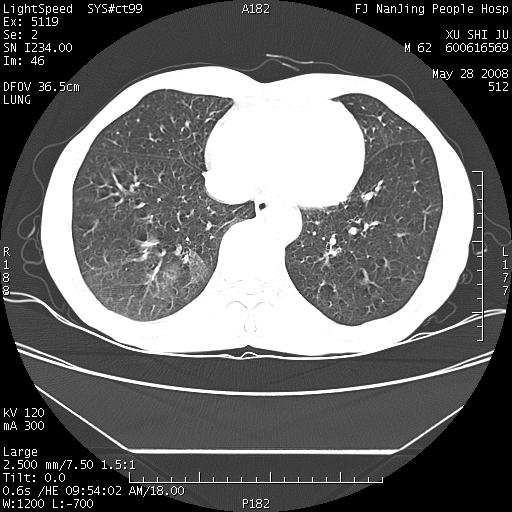

以下是引用杀毒软件在2008-5-28 19:16:00的发言:[br]病灶旁“晕轮征”,考虑肺真菌病

以下是引用qiushi在2008-5-28 20:01:00的发言:[br]空洞周围环状磨玻璃影(日晕征),考虑肺曲霉菌病.

以下是引用yuhongjun在2008-5-29 4:28:00的发言:[br]空洞周围环状磨玻璃影(日晕征),考虑肺曲霉菌病。支持! [br] [br]

以下是引用lrj在2008-5-28 21:10:00的发言:[br]所示应该是正常结构,是对称的,多个层面都有!也不像是内乳动脉或是肿大淋巴结![br]右下肺渗出性病变伴空洞形成,其洞内见一结节,以下诊断都有可能:1 右下肺曲菌感染, 2右下肺结核空洞形成伴曲菌感染!3右下肺结核空洞伴壁内占位形成,虽说后者发生的几率很低 但作为我们应该多考虑一下吧!最重要的结合临床